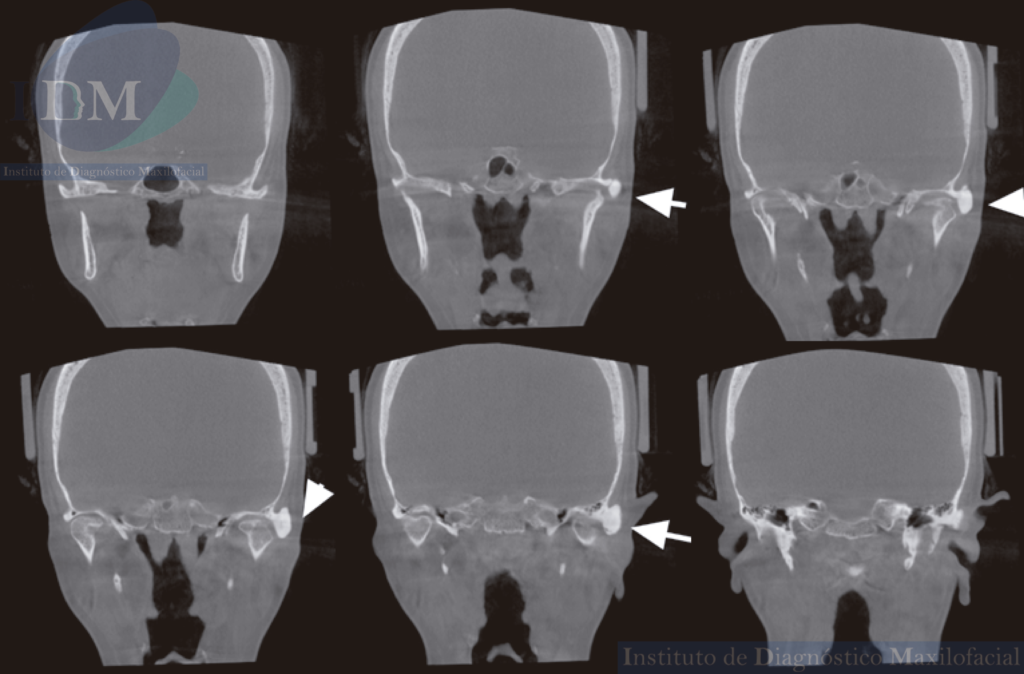

Al observar la tomografía volumétrica de haz cónico (en las reconstrucciones multiplanares, vistas transaxiales y tangenciales) se evidencia la misma imagen de forma redondeada y de densidad ósea que se localiza en la zona infratemporal y en la región posterior del arco cigomático izquierdo próximo a la cavidad glenoidea que a su vez estaría ocasionando un aplanamiento del contorno condilar en su cara externa.

CORTES CORONALES